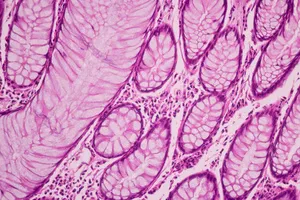

조직검사는 채취한 조직을 특수한 용액에 담가 고정하고, 얇게 잘라 염색하는 등 여러 단계의 과정을 거쳐 현미경으로 관찰하는 복잡한 과정입니다. 병리학 전문가의 현미경으로 조직을 꼼꼼히 분석해야 하기 때문에 시간이 소요됩니다.

유방 결절은 다양한 원인으로 발생하며, 대부분 양성이지만 일부는 악성일 수 있습니다. 조직검사는 결절의 일부를 채취하여 현미경으로 분석하는 검사입니다.